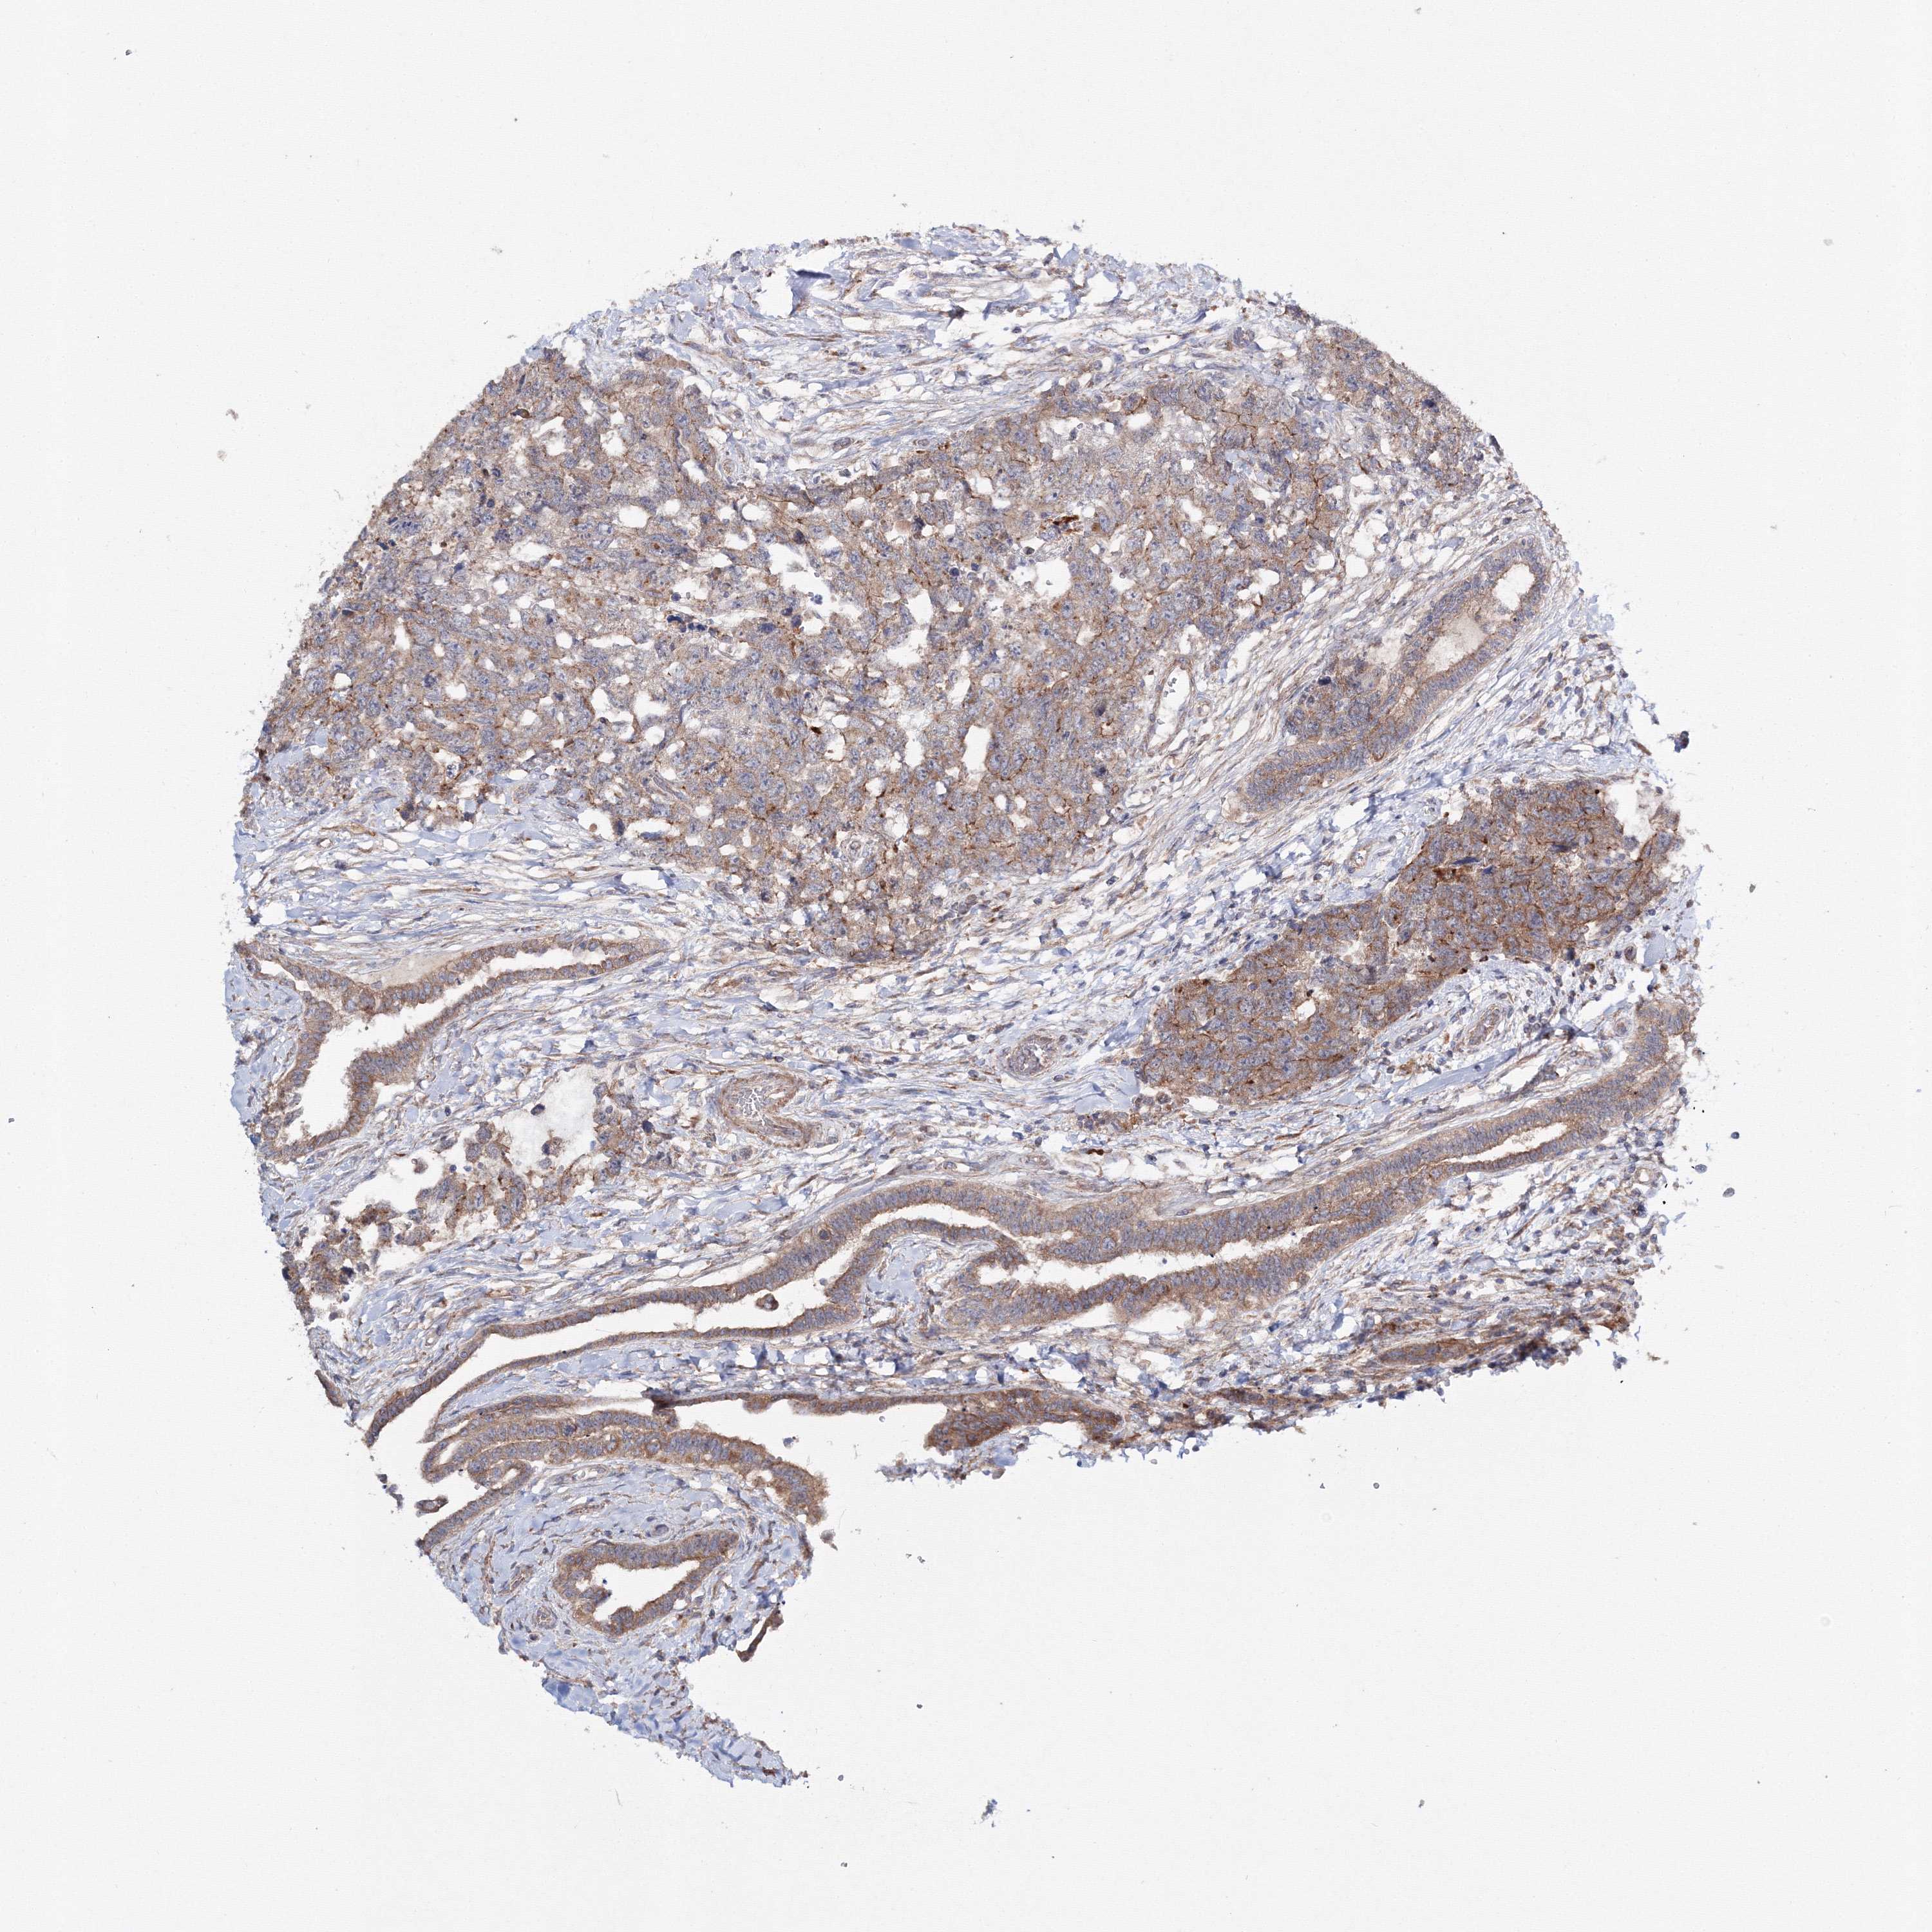

TESTIS CANCER - Protein expressioni

A mouse-over function shows sample information and annotation data. Click on an image to view it in a full screen mode. Samples can be filtered based on level of antibody staining by selecting one or several of the following categories: high, medium, low and not detected. The assay and annotation is described here.

Note that samples used for immunohistochemistry by the Human Protein Atlas do not correspond to samples in the TCGA dataset.

Antibody stainingi

Antibody staining in the annotated cell types in the current human tissue is reported as not detected, low, medium, or high, based on conventional immunohistochemistry profiling in selected tissues. This score is based on the combination of the staining intensity and fraction of stained cells.

Each image is clickable and will lead to virtual microscopy that enables deeper exploration of all samples and also displays staining intensity scores, fraction scores and subcellular localization as well as patient and tissue information for each sample.

Antibody HPA037525

Antibody HPA037526

Staining

High

Medium

Low

Not detected

Intensity

Strong

Moderate

Weak

Negative

Quantity

>75%

75%-25%

<25%

None

Location

Nuclear

Cytoplasmic/membranous

Cytoplasmic/membranous,nuclear

Carcinoma, Embryonal, NOS

Seminoma, NOS